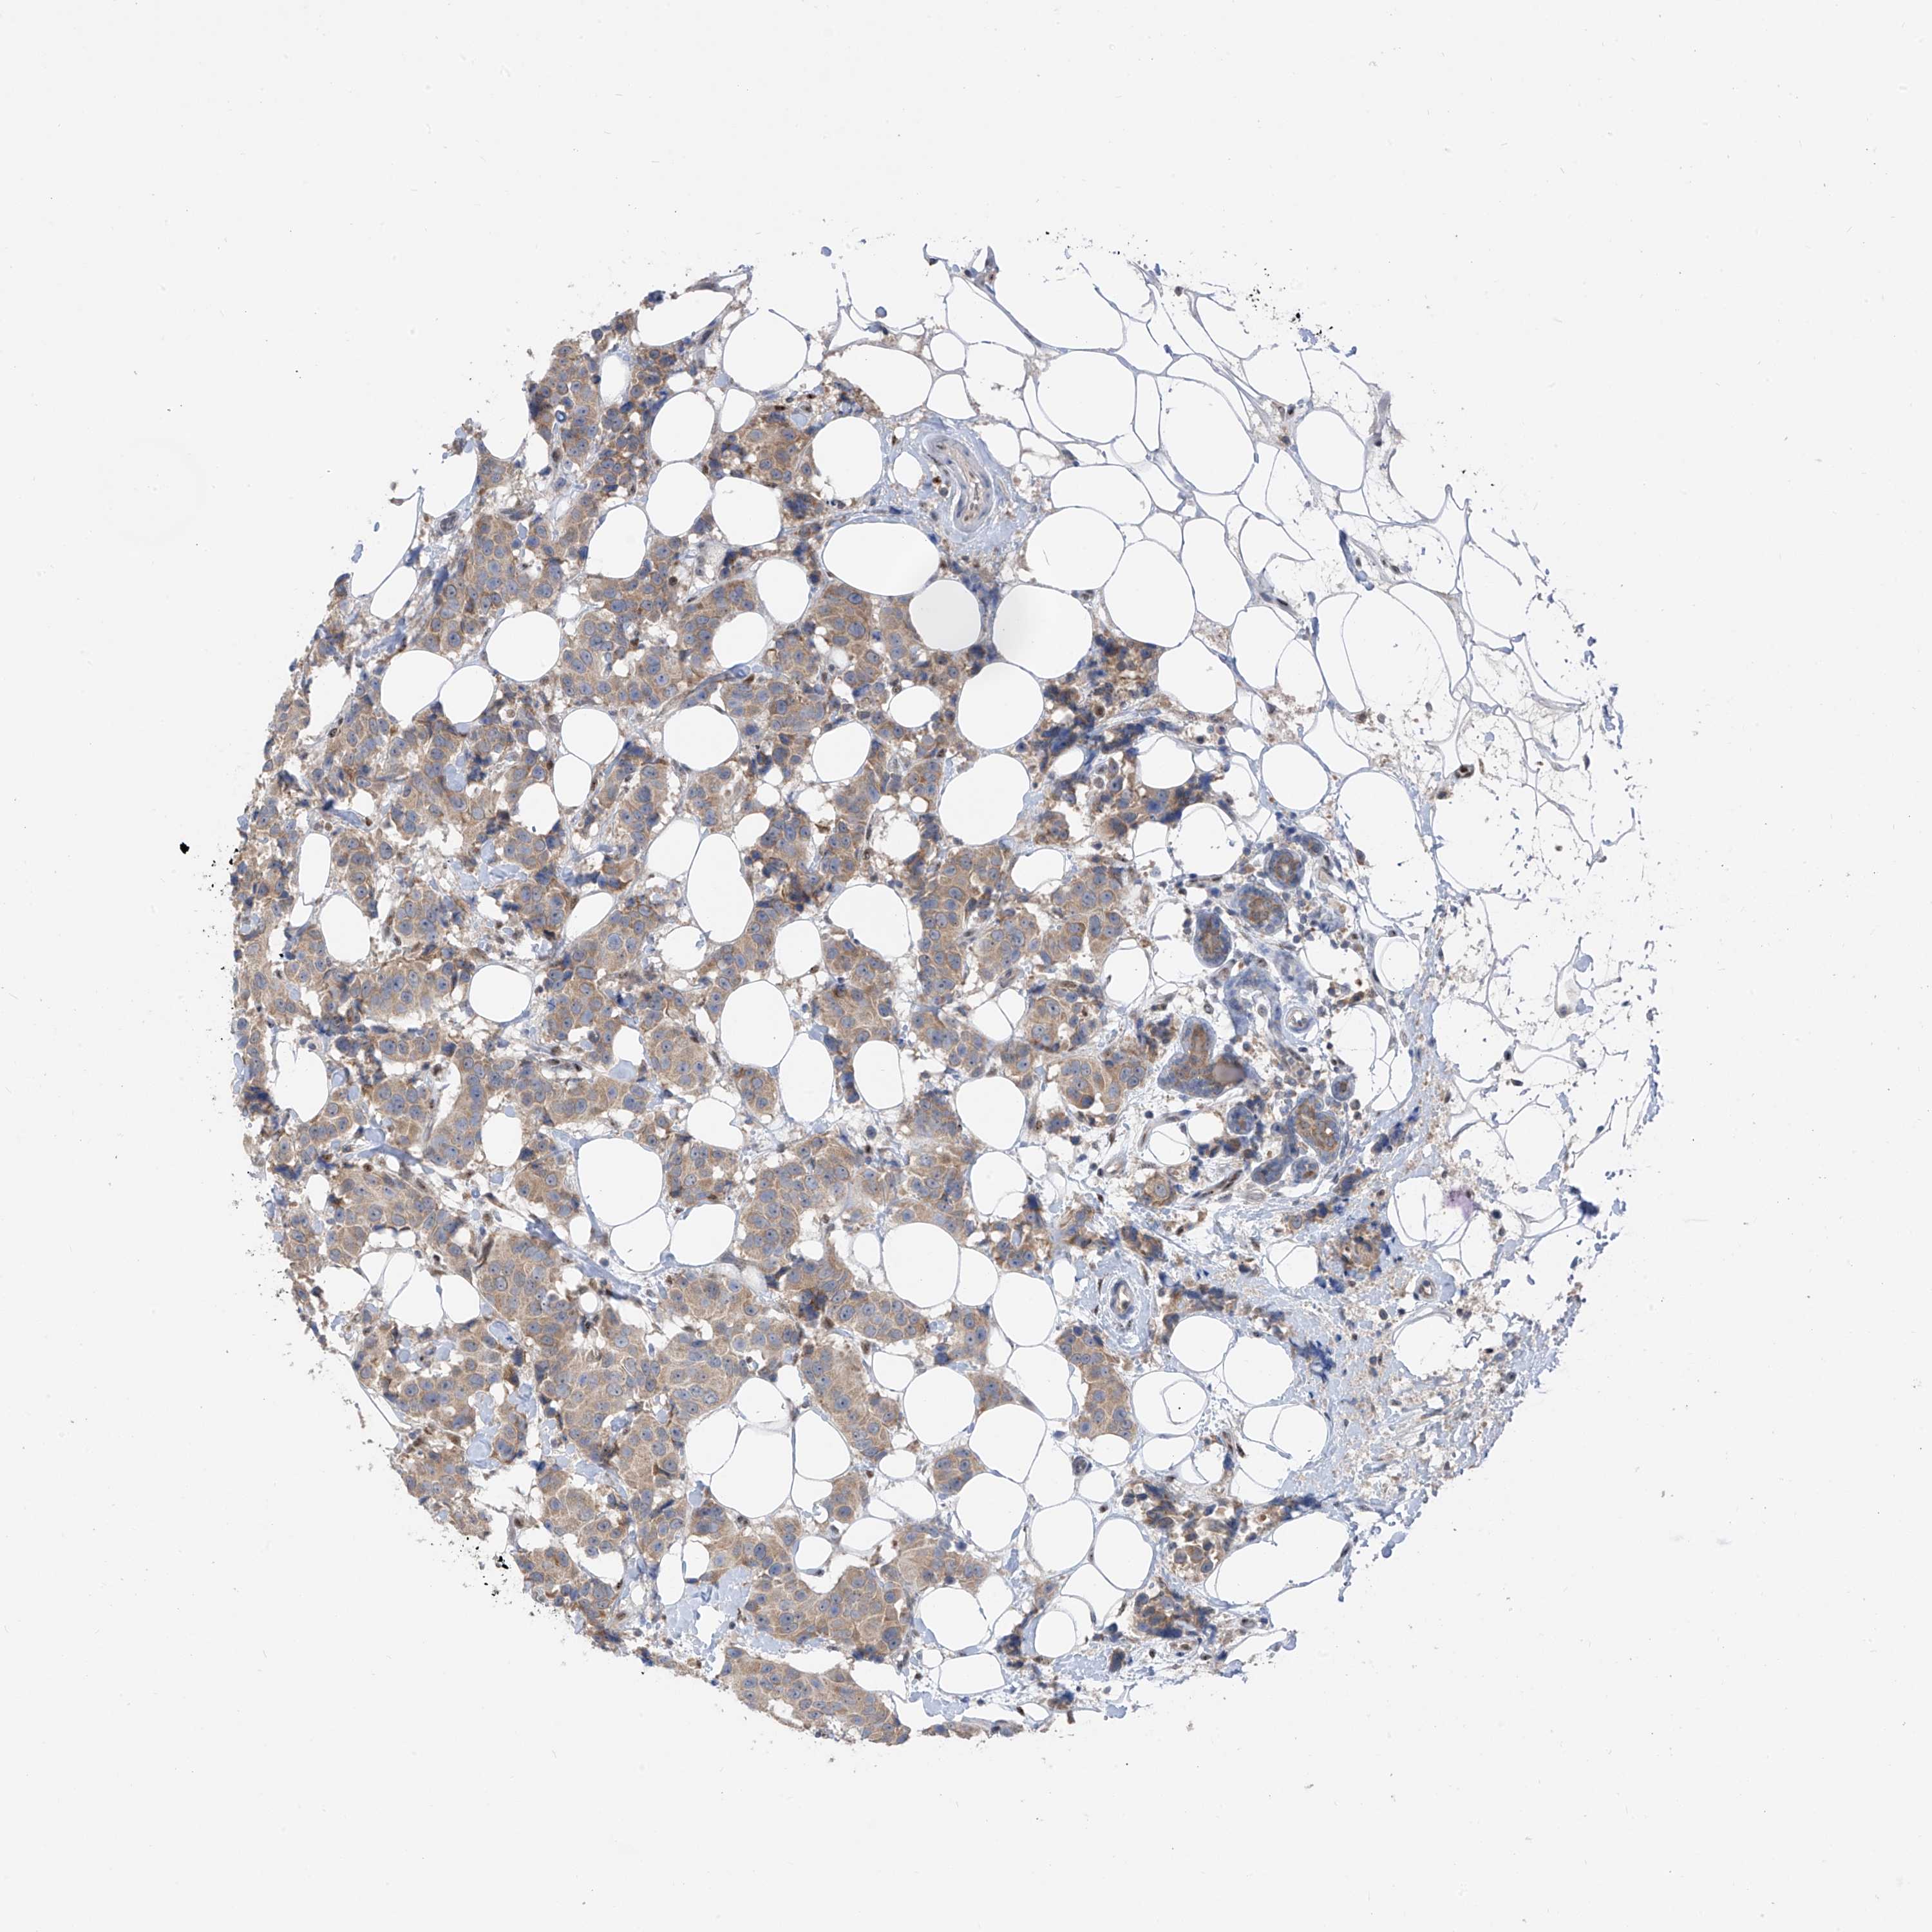

CANCER BREAST CANCER Show tissue menu

BRCA TCGA BRCA VALIDATION PROTEIN EXPRESSION

Breast cancer

Human cancer